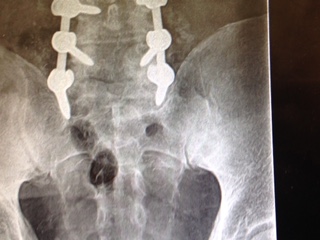

Over the next six months I had further tests done at HSS, Dr. Goodwin consulted with a neurologist, Dr. Reichler, and I researched the doctor and the hospital. After two more appointments, Dr. Goodwin told me that the only good approach to easing my pain was to perform a laminectomy and instrumented fusion on my L4, L5, and S1 vertebrae. I agreed to the procedure and on the morning of December 15th I entered the hospital. Thus began an experience I can only describe as amazing.